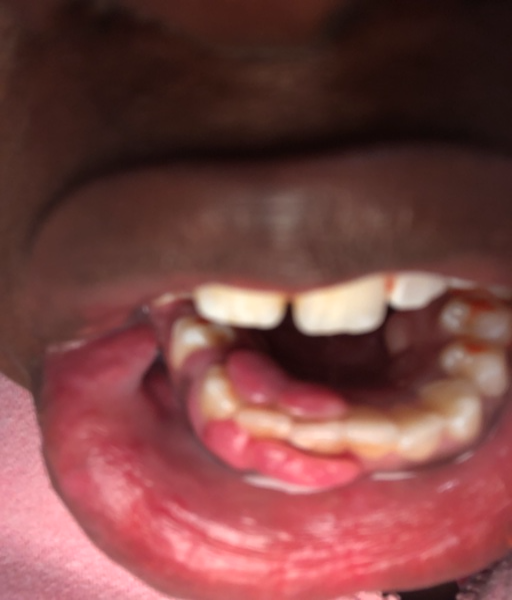

Hi I am 18 and have recently gotten a piercing that is under the tongue. I am going for an wisdom teeth consultation tomorrow and I know they will be taking an x ray that will show the piercing, if I ask politely will it be allowed for them not to tell my mother that I have the piercing and to not show the x rays to her but just me since I am no longer a minor and got the piercing legally. Thank You

As the patient, you have a right to privacy. The office must respect your privacy as an adult, even though you are bringing a parent with you. The office may ask for you to remove the piercing if they need to take a diagnostic radiograph, which can be replaced immediately after it is complete. If the piercing is metal, it can obstruct the image being captured. If you tell the dental/surgical assistant and dentist, I am sure they will respect your wishes and keep your privacy in the matter. It is also important that they discuss pre-op and post-op instructions in regards to the piercing as well.